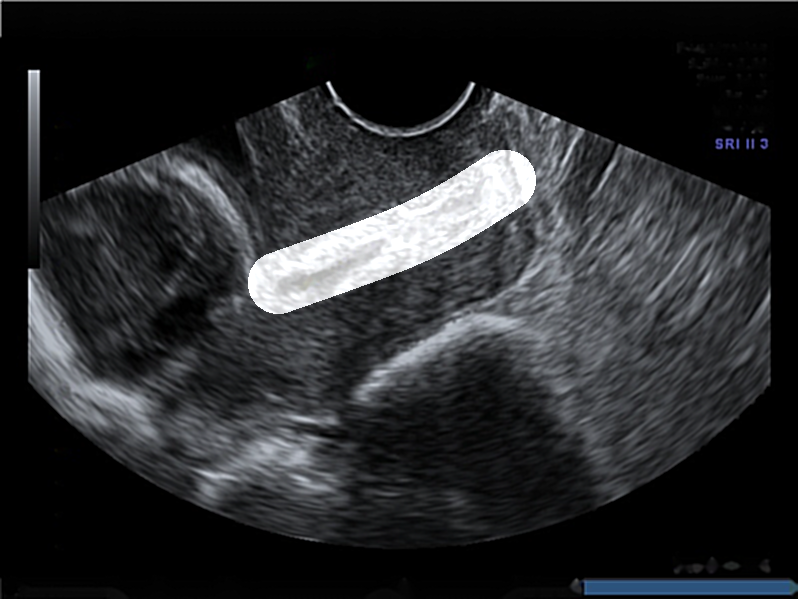

Dataset: The original dataset consists of 354 two-dimensional transvaginal cervical ultrasound images. Data were collected from female volunteers during check-ups conducted in the first and second trimesters of pregnancy. Data includes 319 images of the pregnancy control group and 35 images of premature deliveries which reflects the statistical occurrence of this phenomenon in reality. Note that to get information about image labels, we waited for the pregnancy result of each patient. The data was provided by two different clinics: King’s College London and Medical University of Warsaw. All images have been annotated by several independent gynecologist experts via our own annotation tool. Sample images from the data set are depicted in Fig. 1.

The annotations received contained the study identifier and four control points which allowed for the drawing of cubic Bézier curves that outlined the shape and position of the cervix in the image. Bézier curves were used to create masks for cervical segmentation.